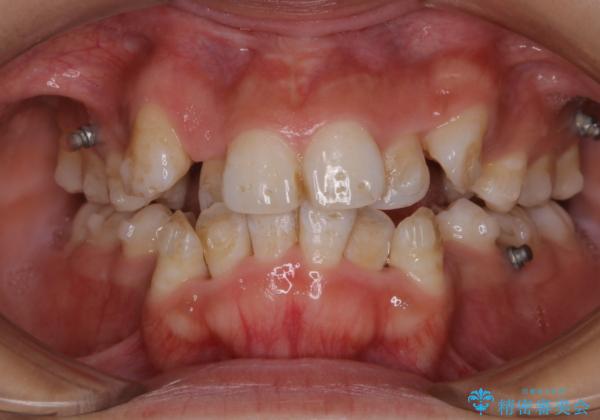

- インビザライン中に、コーヒーによる着色が気になるとのことでした。PMTC60分コースを行いました。

PMTC(保険外治療)は、毎日の歯磨きで落としきれない汚れや、コーヒ、紅茶・タバコのヤニなどの着色も除去します。目には見えない歯と歯の間・歯肉の境目・インビザライン中はアタッチメント周囲などに残っているプラーク(歯垢)もしっかり取り除きます。PMTCでは専門的な機械や材料を使用して、徹底的に汚れを除去するため、虫歯・歯周病・口臭予防などにつながります。